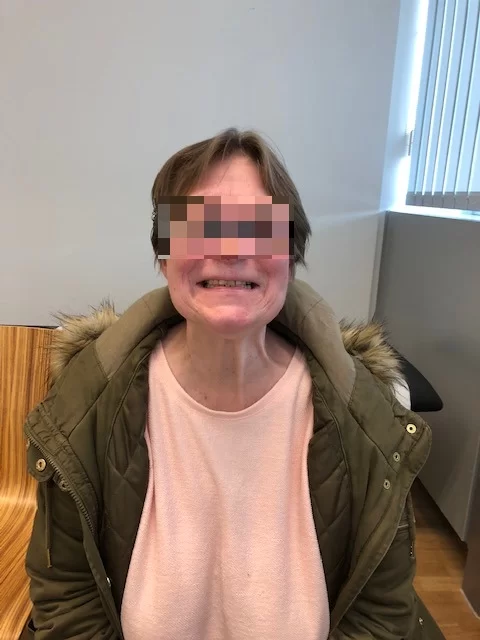

Η ασθενής ανάρρωσε άμεσα και πλήρως, χωρίς νευρολογικό έλλειμα και εξήλθε του νοσοκομείου την 7η μετεγχειρητική ημέρα.

Η μετεγχειρητική εικόνα της ασθενούς ήταν εξαιρετική, χωρίς κανένα νευρολογικό έλλειμα από τις εγκεφαλικές συζυγίες (εγκεφαλικά νεύρα) παρά τη θέση και την έκταση του μηνιγγιώματος.

(Αναπαραγωγή εικόνων με την άδεια της ασθενούς)